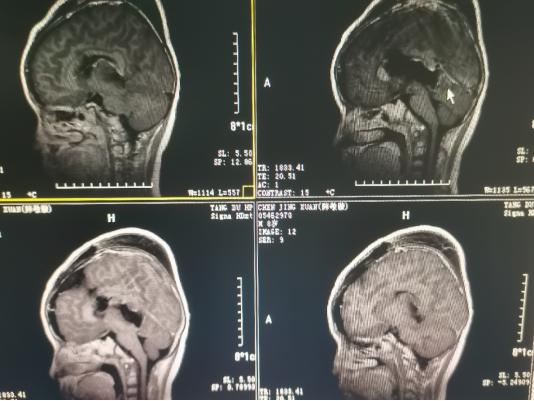

术后影像学资料: